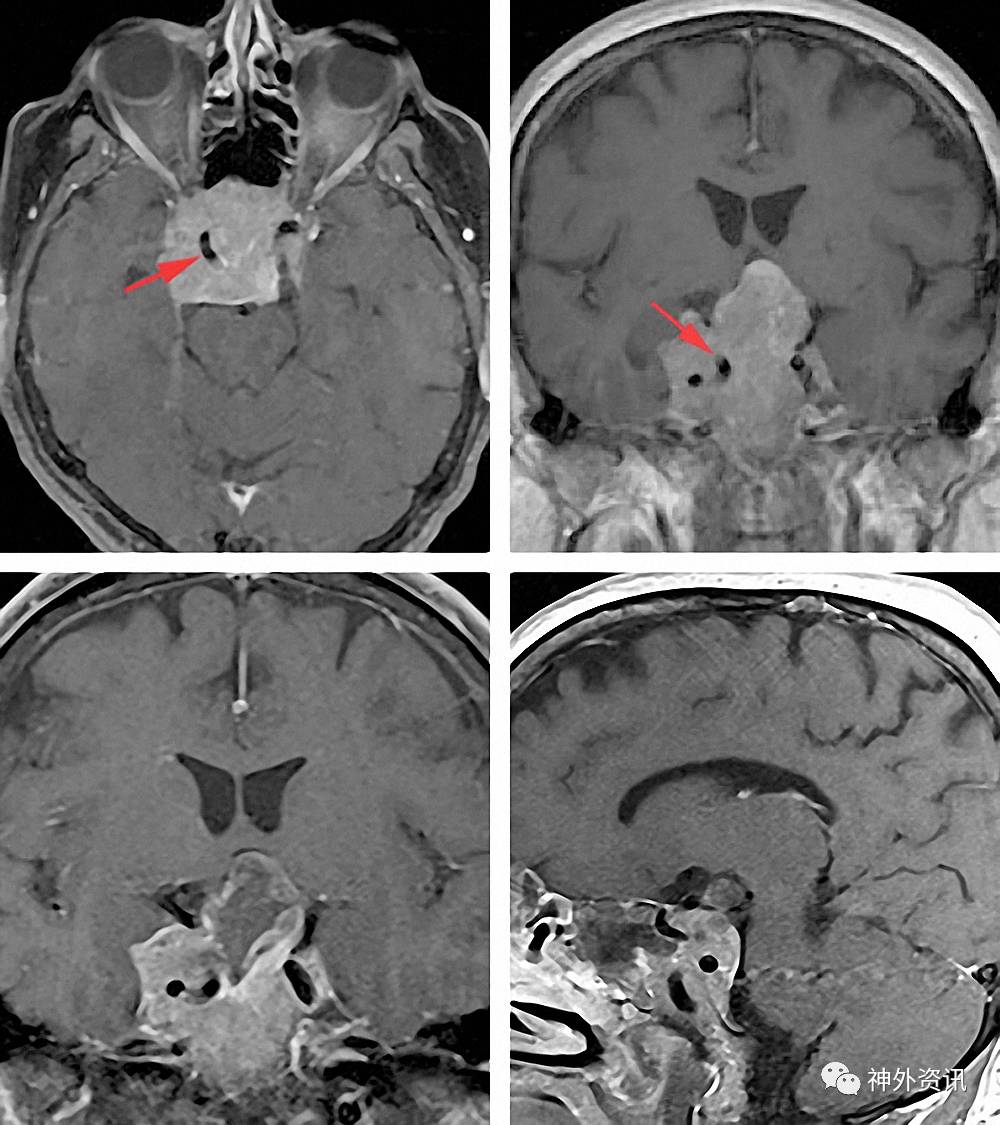

外科医师对颈动脉定位的清晰的理解很关键。该病例扩张的动脉可能被推移到中线位置而很容易在硬脑膜打开以及切除肿瘤的过程中损伤。侵袭性肿瘤可能破坏鞍区的骨性标志,严重影响术中的定位。

图5. 注意右侧穴状扩张的颈动脉,已被侵袭性垂体瘤推移(上图)。肿瘤侵犯颅底,破坏了可识别的骨性标志。笔者在打开硬脑膜时意外撕裂了该动脉,当用棉片轻压撕裂处才得以控制大出血。因患者视力进行性下降,所以仍需继续切除肿瘤(术后早期影像:下图)。

如果动脉破损处无法立即准确定位并封闭,则应在术区填塞棉片控制出血,中止手术,立即行动脉造影排除假性动脉瘤。